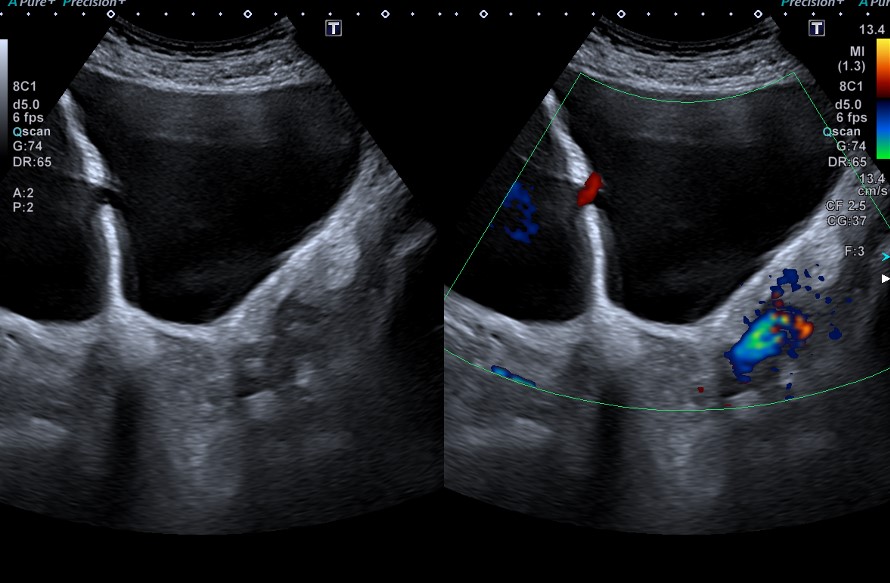

Riñones de tamaño y morfología normales. No observamos litiasis ni dilatación de la vía urinaria. A nivel de la vejiga presenta un tabique con comunicación a una gran cavidad en la pared lateral derecha que da la impresión de que existen dos vejigas urinarias. No hay lesiones parietales. Próstata 32 cc. Volumen premiccional de la cavidad mayor 350 cc y posmiccional 210 cc.

Vejiga urinaria con presencia de jets ureterales, de paredes lisas con un gran divertículo en la pared lateral derecha de 543 cc premiccional que vacía a la mitad en posmiccional 310cc (57%).Volumen vesical premiccional 620cc y posmiccional 179 cc (28%).